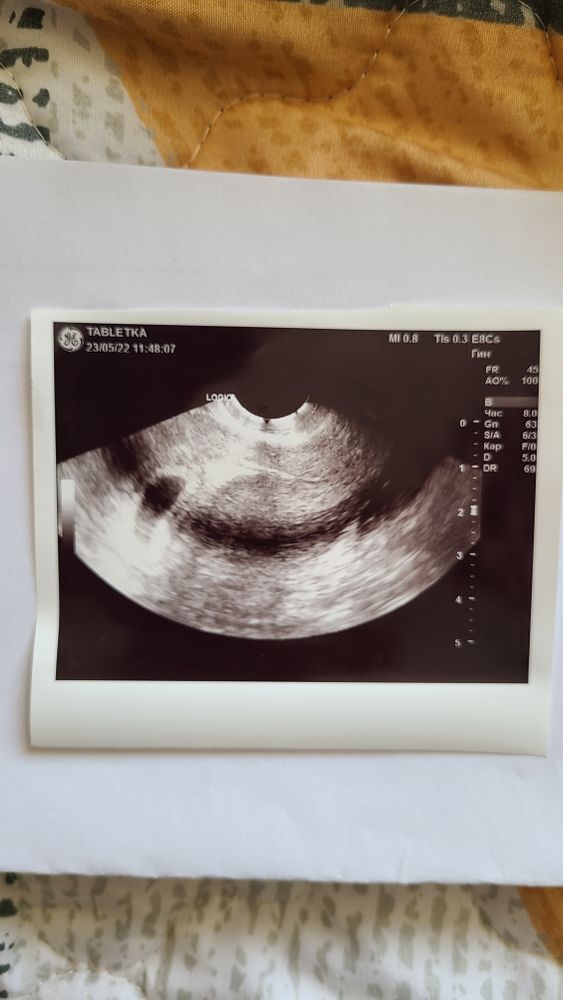

Эмбриончик не визуализируется

Получается сейчас у меня начало 5 недели, на 4 неделе было одно плодное яйцо 5 мм и желточный мешочек 2,5 мм. Эмбриончика врач не увидела, сказала, что возможно из-за гипертонуса (я конечно испугалась из-за кровотечения)

Прописала но-шпу, попаверин и УЗИ через неделю. У кого так было, что на 5 неделе нет ещё эмбриона? Пытаюсь не волноваться

Не переживайте. Я тоже сегодня на узи была и так же 5,4 н. 8мм пя. Жм - 3мм. Эмбрирна нет. Он позже появится чуть время надо. Я пошла просто не вытерпела.